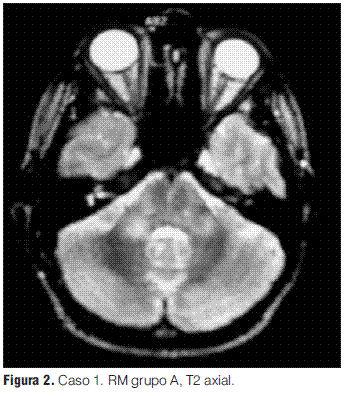

Grupo A: EMDA a pequeñas placas, lesiones menores a 5 mm de diámetro.

Se realizaron RM en la primera semana de evolución de la enfermedad en todos los pacientes, revelando en todos los casos alteraciones características (tabla 3).